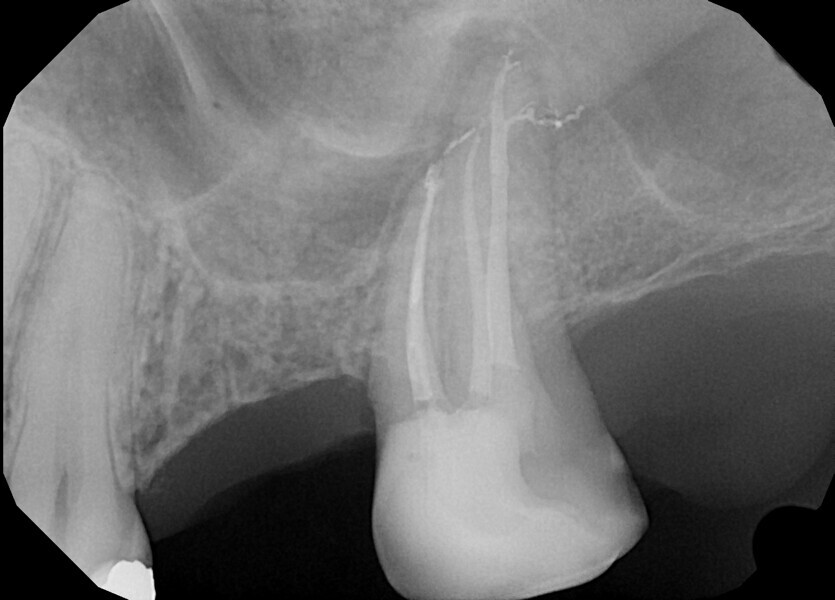

Fig.: 2

Most technical instructions advise dental practitioners to use files in three to four continuous pecking motions, every move advancing a little bit more without removing the file, and then to remove the file from the canal, clean the instrument, irrigate the canal and repeat, until the operator reaches the apical area. This kind of approach creates a pumping motion and pushes all the debris laterally and towards the apical area, respectively. Then the final irrigation protocol is performed. It is much more difficult from the beginning because of all the blockages in the lateral anatomies and ramifications created with the preparation (Fig. 2).